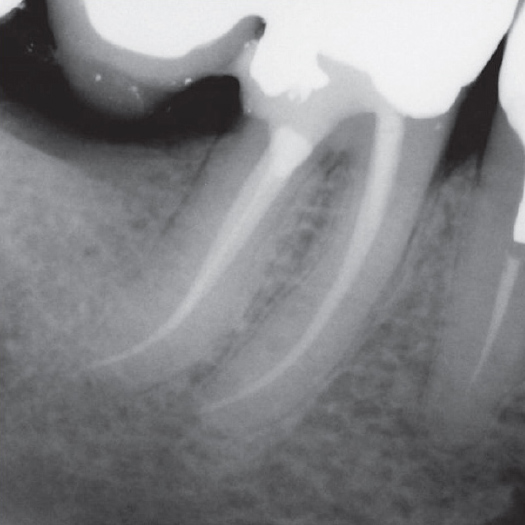

After

After Root Canal treatment